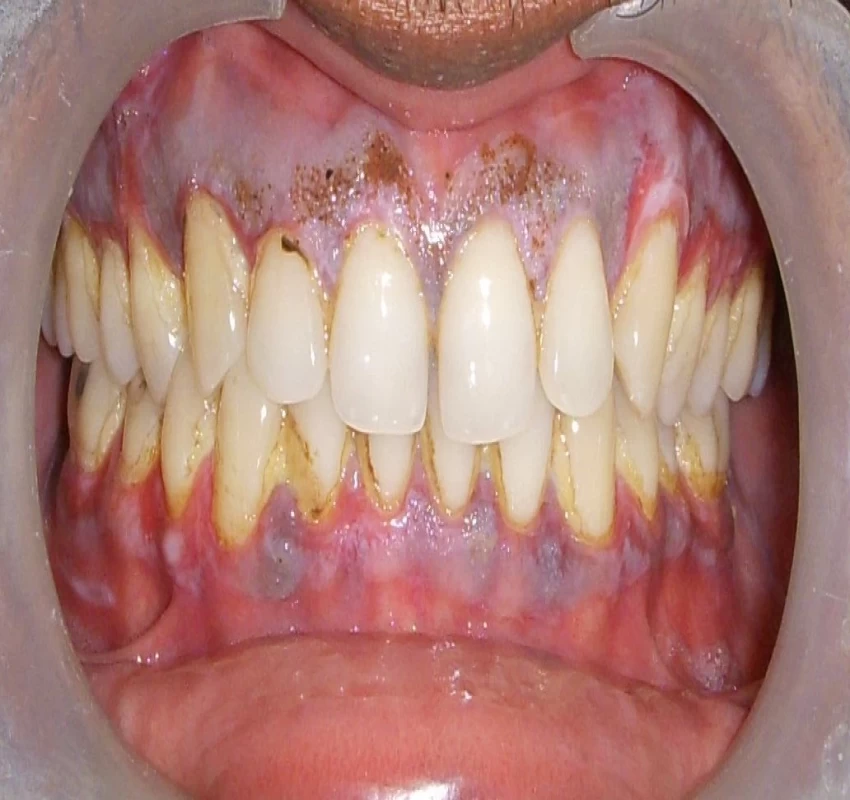

The term LASER is an acronym for 'Light Amplification by the Stimulated Emission of Radiation'. As its first application in Dentistry by Miaman, in 1960, LASER has seen various hard and soft tissue applications. In the last two decades, there has been an explosion of research studies in LASER application. Soft tissue application includes treatment of premalignant lesions and conditions such as leukoplakia, lichen planus, OSMF, treatment of ulcers, excision of traumatic fibromas etc. Besides these, low-level LASER therapy also proved to have biostimulative, regenerative, analgesic, and anti-inflammatory effects on temporomandibular disorders (TMDs) & orofacial pains. Thus, the use of the LASER proved to be an effective tool to increase efficiency, specificity, ease, and cost, and comfort of the dental treatment.